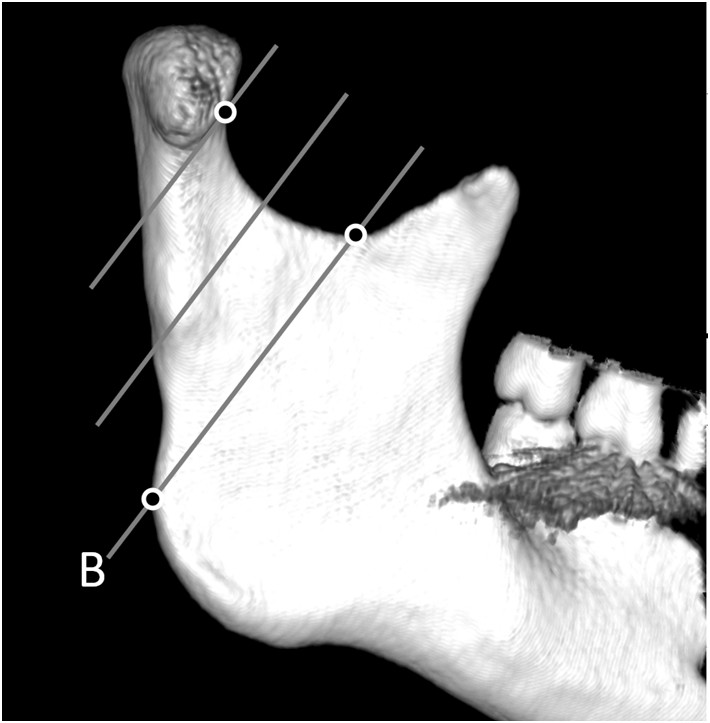

Wprowadzenie w 2018 roku klasyfikacji złamań wyrostka kłykciowego żuchwy wg Kozakiewicza (przedstawiona na rycinie) było związane ze zniknięciem z obserwacji klinicznych złamań szyjki żuchwy (w klasyfikacji SORG/AO). Wszystkie wysokie złamania szyjki stały się złamaniami głowy żuchwy typu C, zaś niskie złamania szyjki, stały się złamaniami podstawy wyrostka kłykciowego. Nie odzwierciedlało to prawdziwej częstości występowania różnych złamań wyrostka kłykciowego. Wskaż prawdziwe stwierdzenie dotyczące klasyfikacji wg Kozakiewicza:

Budowa żuchwy jest przystosowana do przenoszenia obciążeń zgryzowych. Siła mięśni w czasie gryzienia powoduje naprężenia w wyrostku kłykciowym. Miejsca te zaznaczono 2 liniami (przerywaną i ciągłą). Wskaż prawdziwe stwierdzenie: